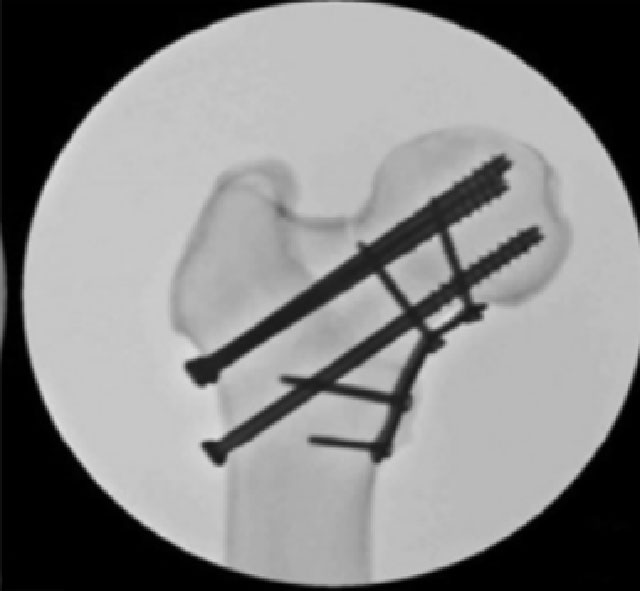

②空心钉+内侧支撑钢板:在垂直方向上添加内侧支撑钢板以抵抗剪切力,可以减少此类损伤传统上较高的并发症发生率。在一些生物力学和临床研究中,与单纯螺钉固定相比,内侧支撑钢板增强的空心螺钉显示出更大的生物力学稳定性和更高的愈合率。

空心钉+内侧支撑钢板